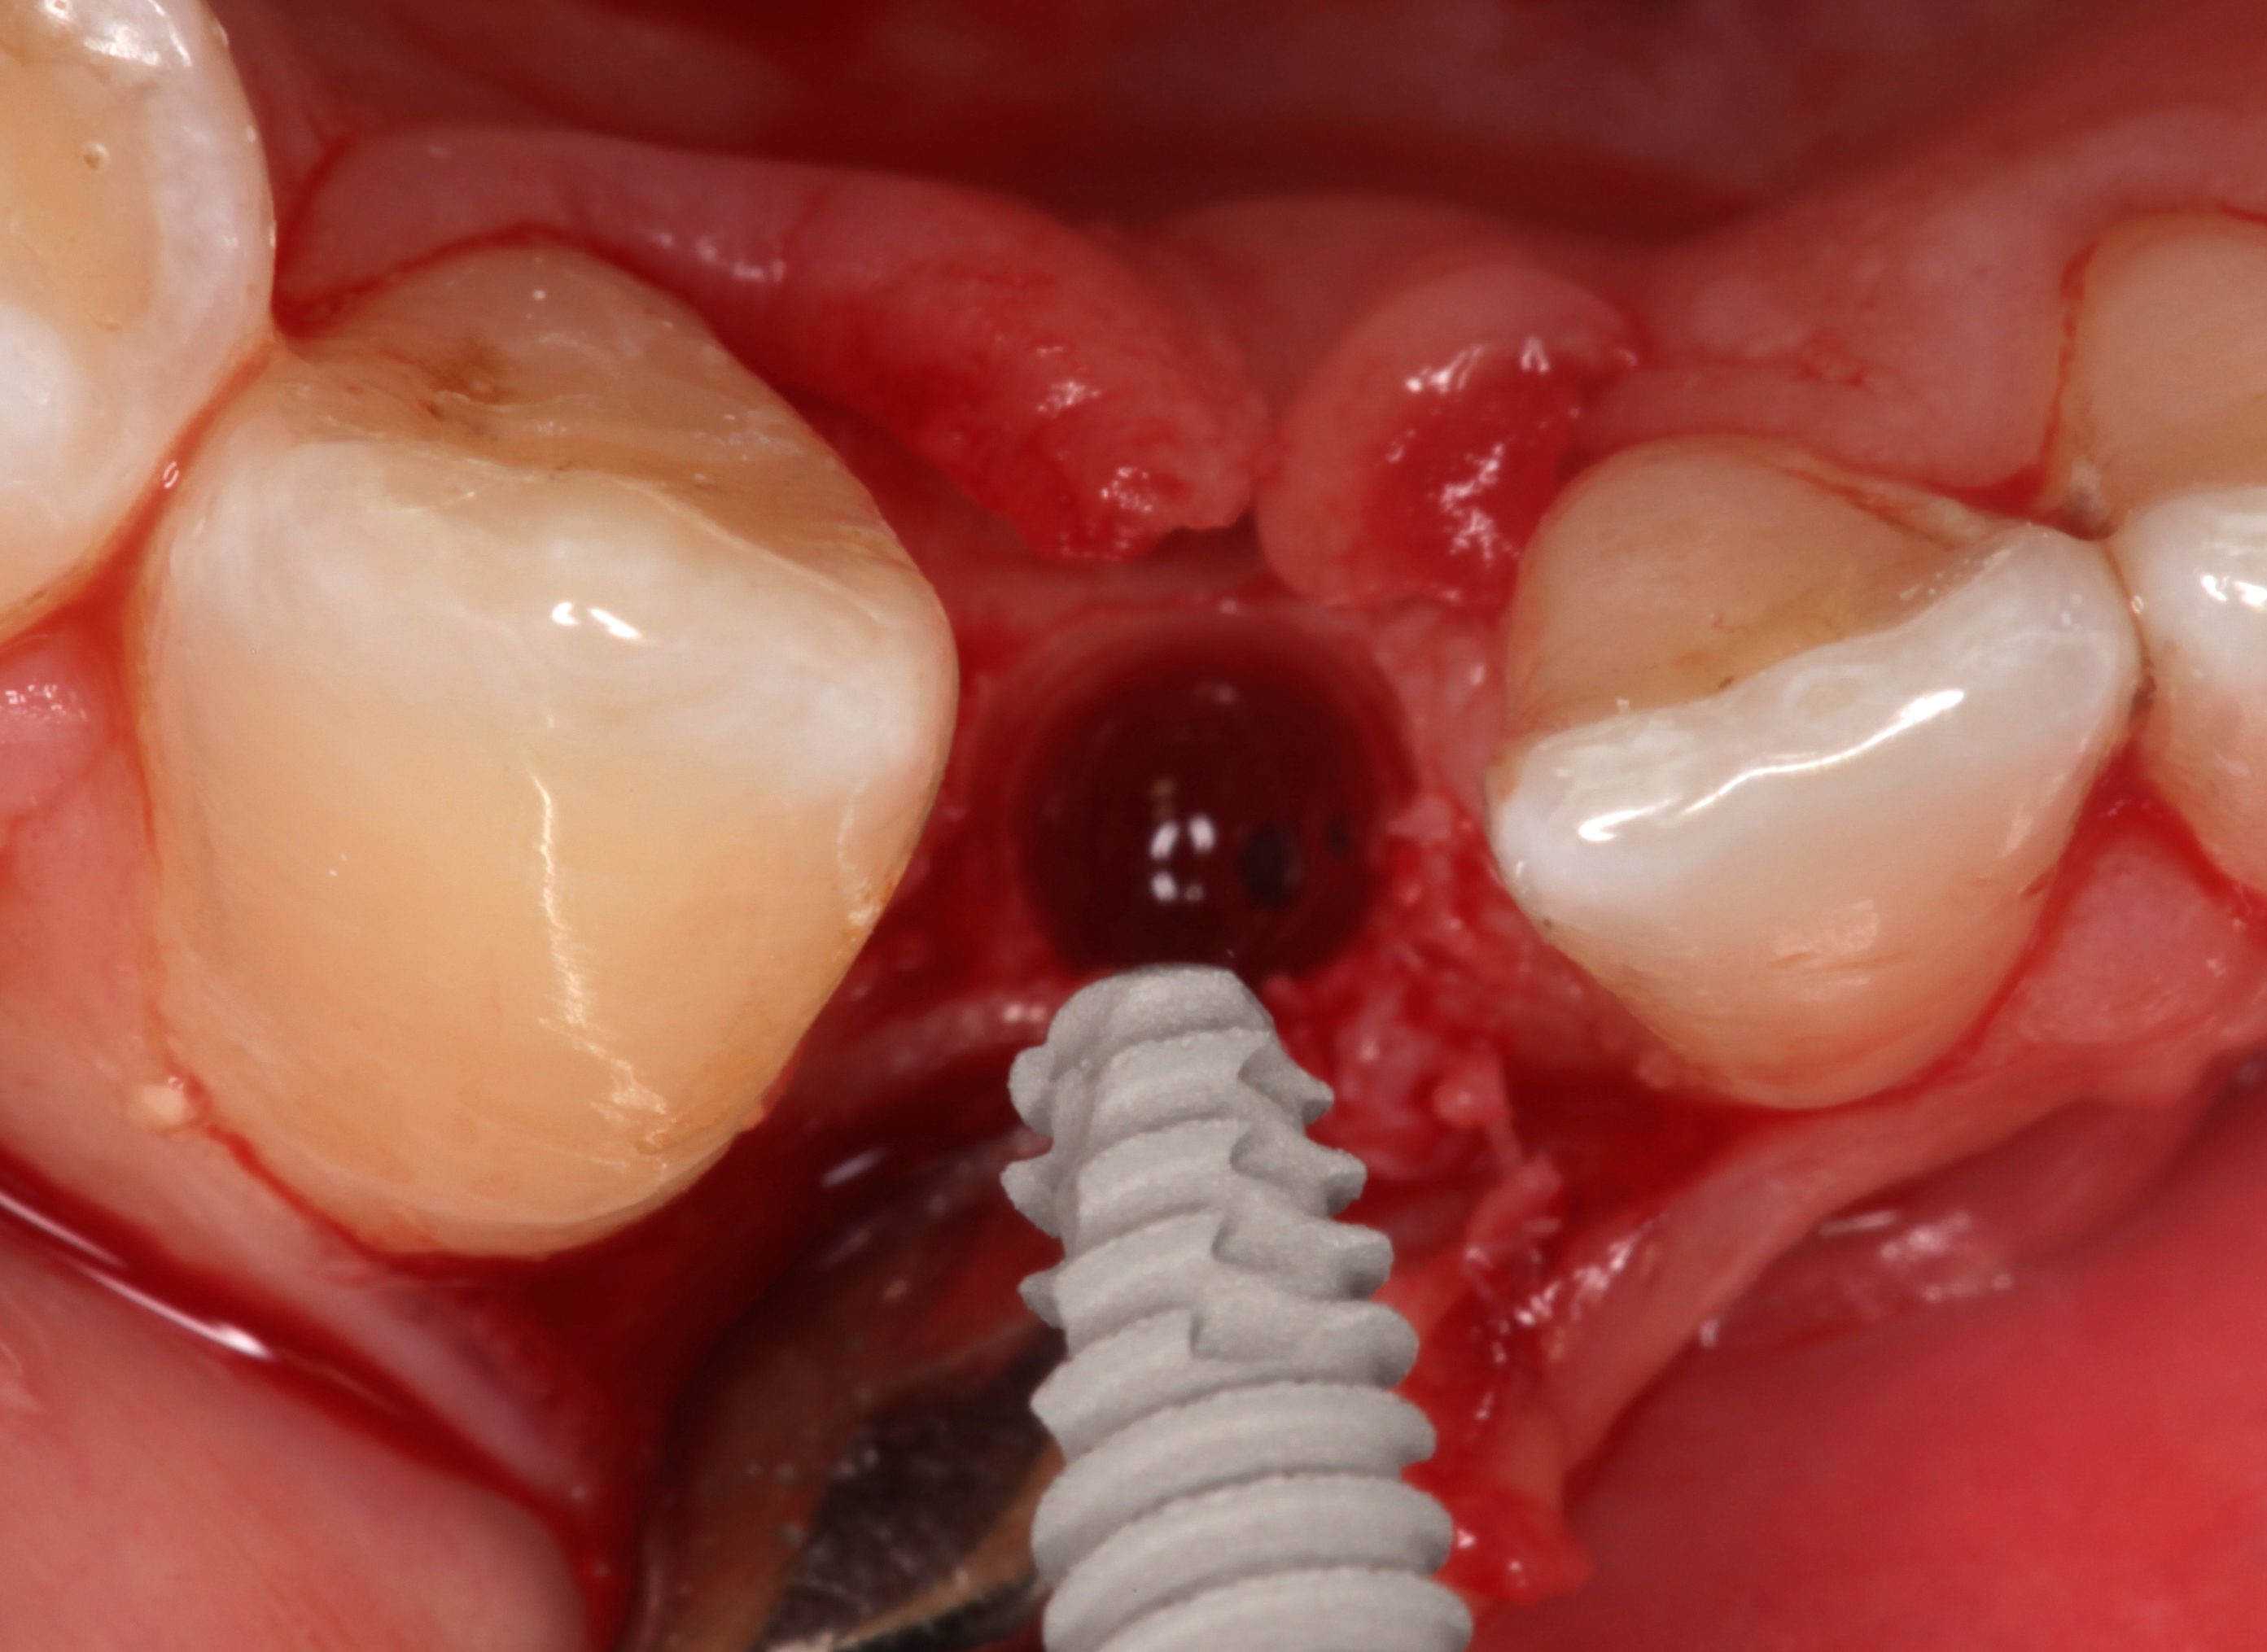

Clinical examination showed 2 mm of buccal recession with a shallow vestibule and absence of keratinized attached gingiva against the crown with 8 mm of circumferential pocketing accompanied by bleeding upon probing (Figure 15 and Figure 16). A periapical radiograph showed a symmetrical vertical osseous defect causing the loss of 50% of the bone around the implant (Figure 17). Because the patient had made a significant investment of time and finances to replace her lost tooth with the implant, she desired that the implant and restoration be retained, if feasible.

A surgical flap procedure was performed with the intent of thoroughly debriding the granulomatous tissue from the osseous defect (Figure 18 and Figure 19), mechanically and chemically detoxifying the surface of the implant (Figure 20 through Figure 22), and grafting the infrabony component of lesion with bone xenograft (Bio-Oss®, Geistlich Pharma, www.geistlich-na.com) in an attempt to reduce the vertical defect (Figure 23). To concurrently resolve the mucogingival problem, the plan called for placing a dermal allograft (Dermis Allograft, DENTSPLY International, www.dentsply.com) on the buccal (Figure 24) and then replacing the flap (Figure 25).

Fig 15. The implant-supported restoration of tooth No. 19 presented with a lack of attached keratinized gingiva, shallow buccal vestibule, and 2 mm of buccal recession.

Figure 15

Fig 16. The restoration exhibited an 8-mm pocket upon probing, with bleeding on the buccal aspect.

Figure 16

Fig 18. A full-thickness flap from teeth Nos. 18 to 20 revealed granulomatous tissue in the circumferential defect around implant No. 19.

Figure 18

Fig 19. The circumferential defect was debrided. Note excess cement extending apically from the margin of the crown into the defect; residual cement has been shown to be complicit in the development of peri-implant disease.